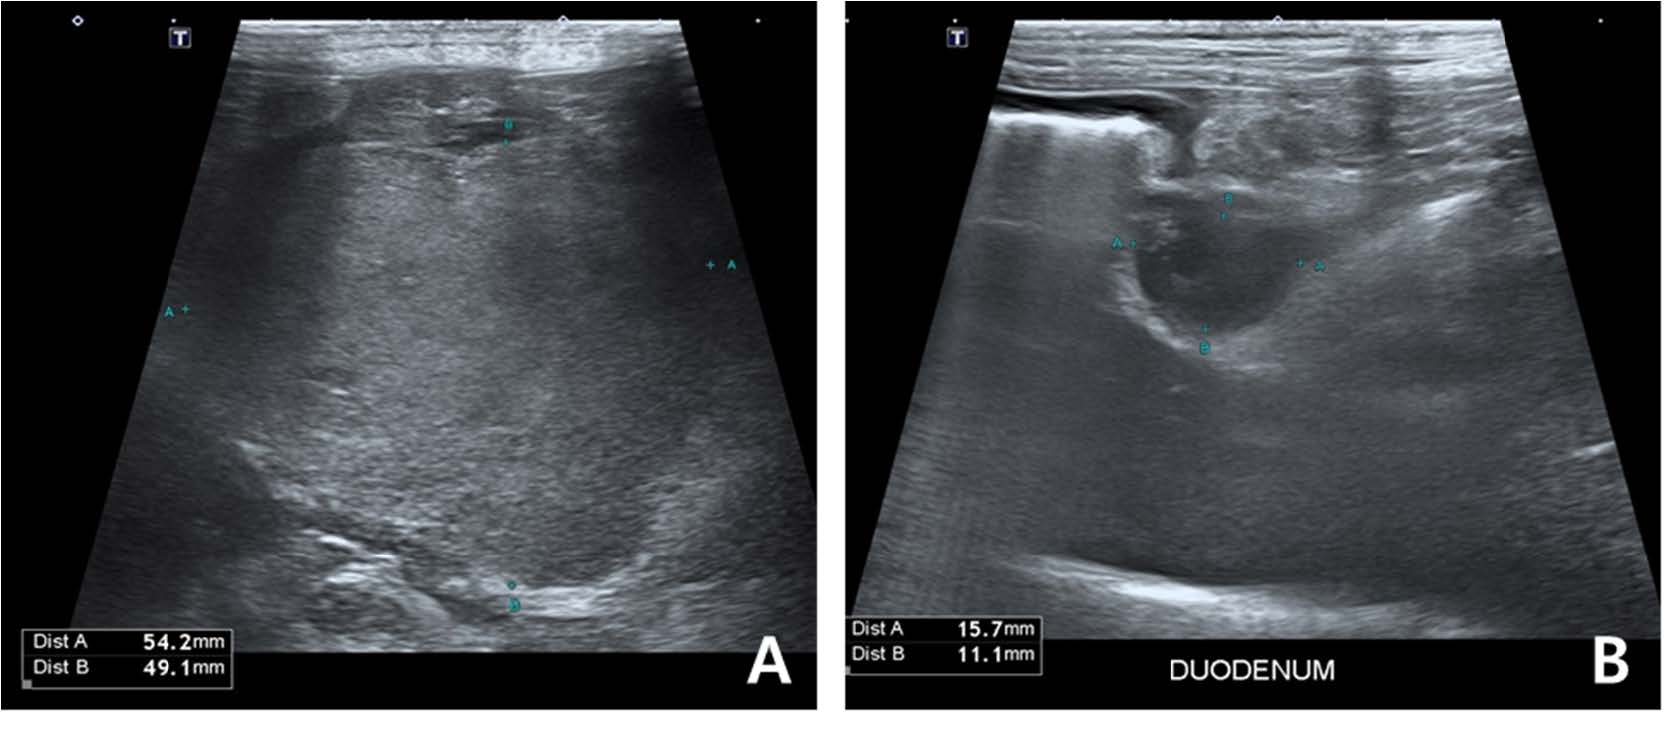

第190天,经过大约3个月的verdinexor单抗治疗后,患者出现血清蛋白水平升高、严重的胃肠道症状和倦怠。腹部超声发现一个巨大的腹腔内肿块(54.2×49.1 mm),推测为肝淋巴结肿大,十二指肠乳头处的肿块(8.1×20.2 mm)及胰腺体部的低回声肿块(11.8×8.7 mm)提示转移(下图)。

↑ 第189天腹部超声。在腹腔内观察到一个直径约为5厘米的肿块,怀疑是肿大的肝淋巴结(A)。在十二指肠水平还发现了一个额外的肿块(B)。